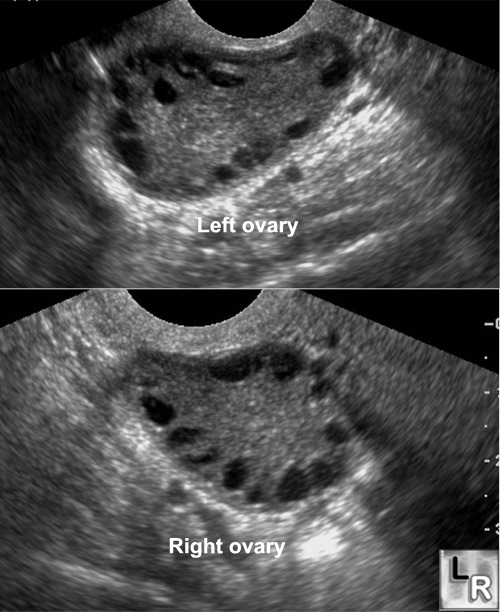

From teachmeobgyn.com

Polycystic Ovary Syndrome PCOS Fertility Ultrasound TeachMeObGyn White Spots On Uterine Wall Cervicitis is an inflammation of the cervix, the lower, narrow end of the uterus that opens into the vagina. The conditions may be caused by. Various strains of the human papillomavirus, also called hpv, play a role in causing most cervical cancers. The uterus can be affected by many different conditions, some of which have similar symptoms. The cervix is. White Spots On Uterine Wall.

From www.researchgate.net

Transvaginal ultrasound of the ovary Download Scientific Diagram White Spots On Uterine Wall The cervix is the lower part of the uterus that connects to the vagina. The conditions may be caused by. Cervicitis is an inflammation of the cervix, the lower, narrow end of the uterus that opens into the vagina. The patient may be asymptomatic or report symptoms of discharge, dysmenorrhea, pelvic pain, or. Various strains of the human papillomavirus, also. White Spots On Uterine Wall.

Polycystic Ovarian Syndrome (PCOS) Stepwards White Spots On Uterine Wall The uterus can be affected by many different conditions, some of which have similar symptoms. Various strains of the human papillomavirus, also called hpv, play a role in causing most cervical cancers. Nabothian cysts are harmless bumps that sometimes form when skin cells clog glands in the cervix. The conditions may be caused by. The cervix is the lower part. White Spots On Uterine Wall.